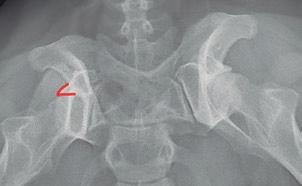

Displasia de cadera (I): etiopatogenia, signos clínicos y pruebas diagnósticas 26

• Patología de la piel y el oído